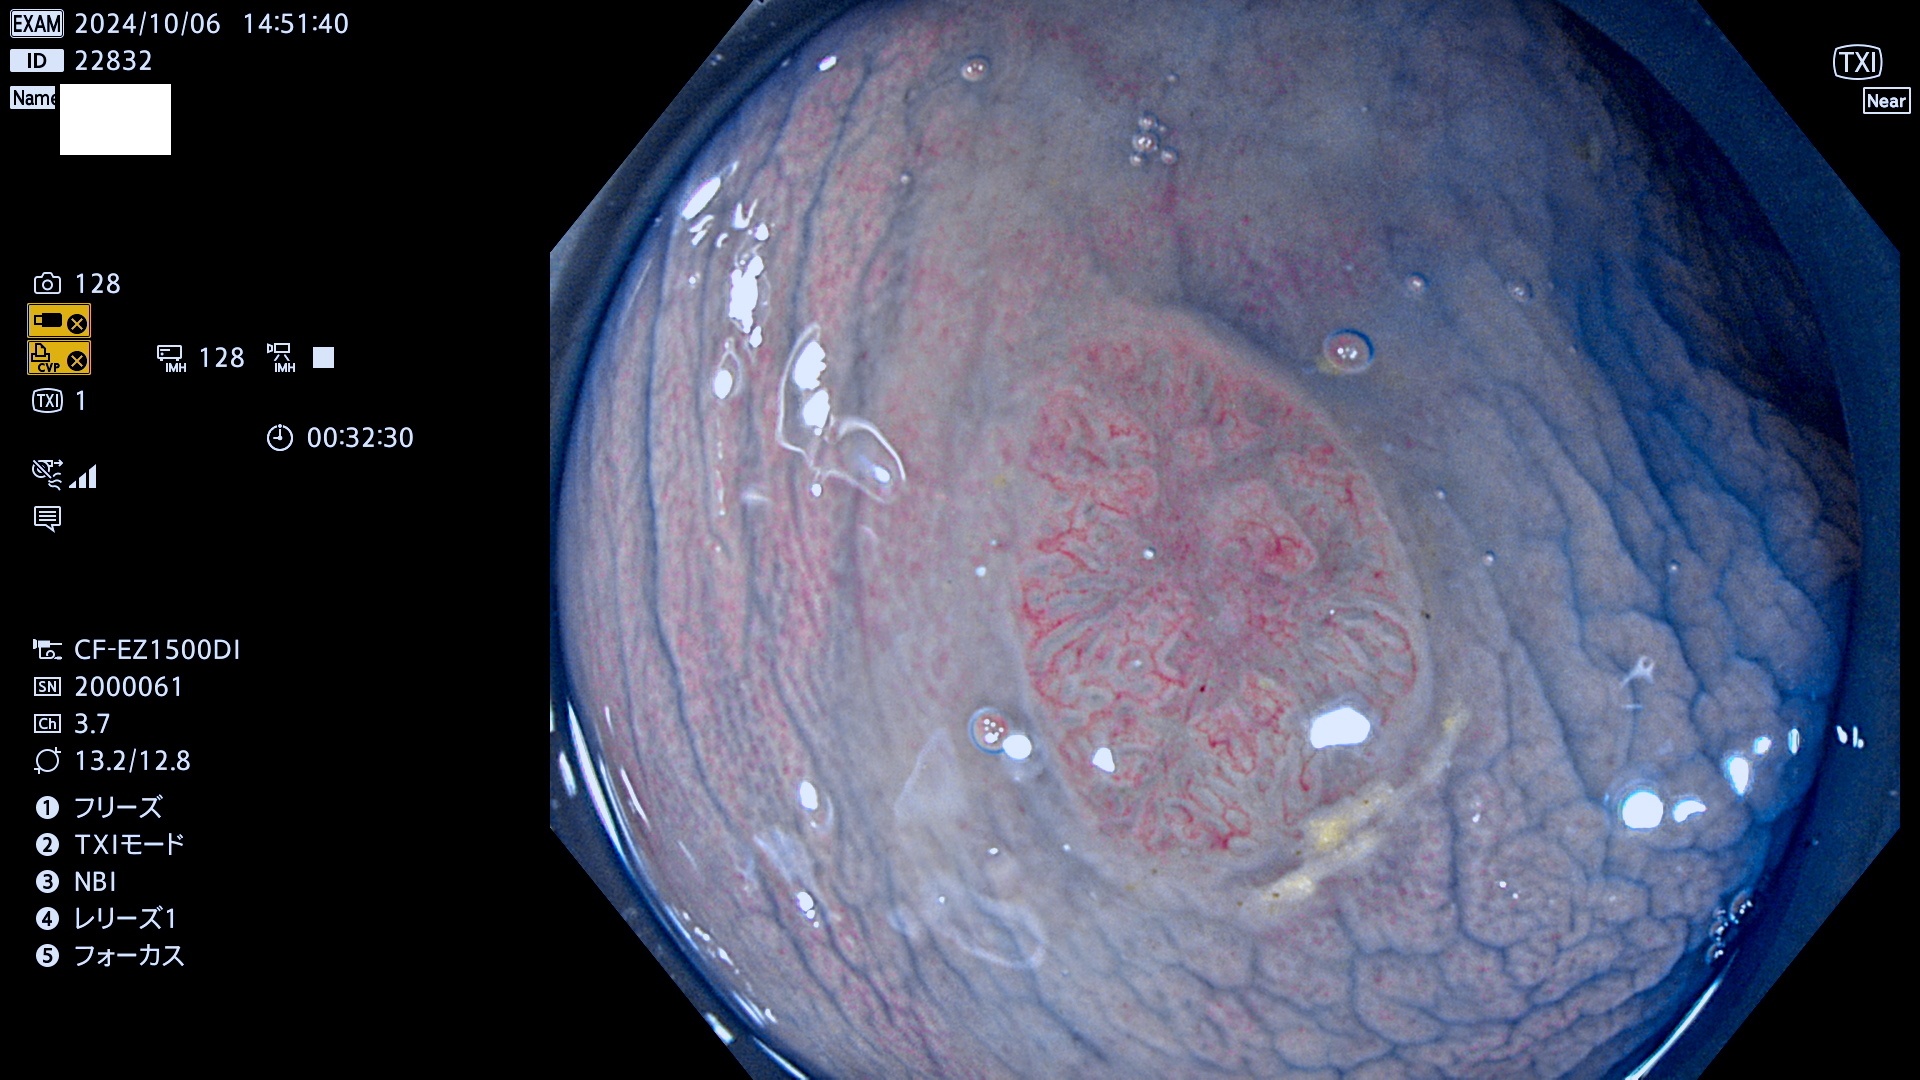

今週のUb、Uc型腺腫

完全に平坦な物をUb、陥凹している物をUcと呼びます。最も発見が難しく危険な病変です。

専門的)Uc=De Novo癌? 内視鏡の解像度が低かった時代、このような説もありました。しかし今日の高精度内視鏡では良性の微小なUc型腺腫が日常的に見つかります。私見ですが「Ucこそが多段階発癌(Adenoma-Carcinoma Sequence)のMain Route」と考えます。

毎週の検査(木・金・土・日)に発見されたUb、Uc型・腺腫を、その週の日曜の夜にUPし1週間、提示します。

抽出の対象期間 2024年10月3日〜10月6日の4日間(48件の検査)9件 (9/48=18%)